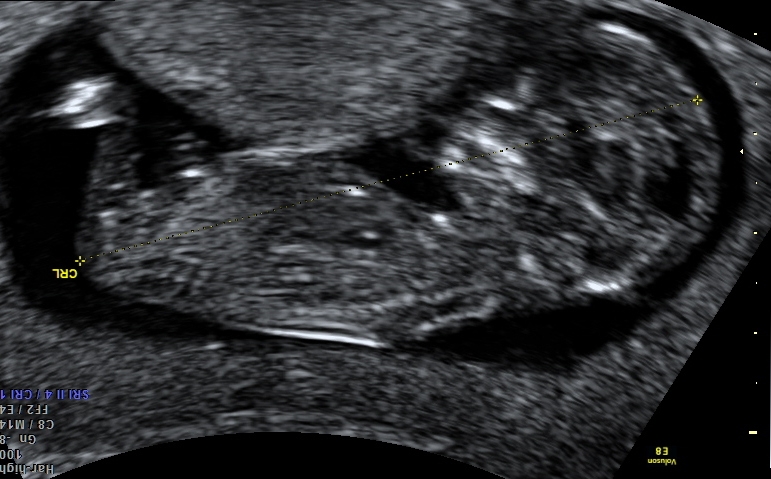

I've just had my 12 week scan and this is the best photo I got. Can you see a nub?

Anyone care to guess boy or girl? We swayed girl but I am ok with hearing boy so please be honest :)